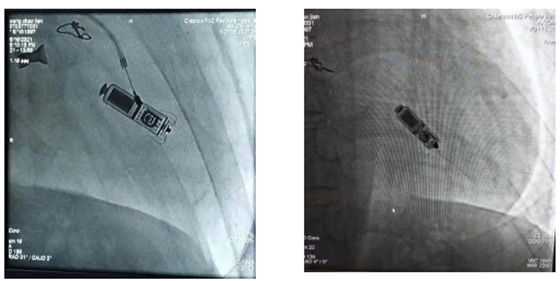

6月16日,我院心内科在中科大第一附属医院徐健团队帮助下成功植入池州首例无导线Micra起搏器。

我院心内科团队基于患者的病情和综合情况考虑,再与患者家属充分的沟通,选择了目前世界上最先进、体积最小的Micra无导线起搏器进行植入。

Micra起搏器相较于传统起搏器仅有胶囊大小,无需植入心内膜导线,也无需在胸前皮下制作囊袋放置脉冲发生器(起搏器),直接植入在心腔内,无伤疤、无切口,减少了创伤与感染风险,患者在植入后几乎感觉不到起搏器的存在,大大提升了患者的生活质量。此外,患者植入该起搏器后仍然可以做1.5T/3.0T全身核磁共振等扫描检查,满足了患者之后疾病诊断的需求。